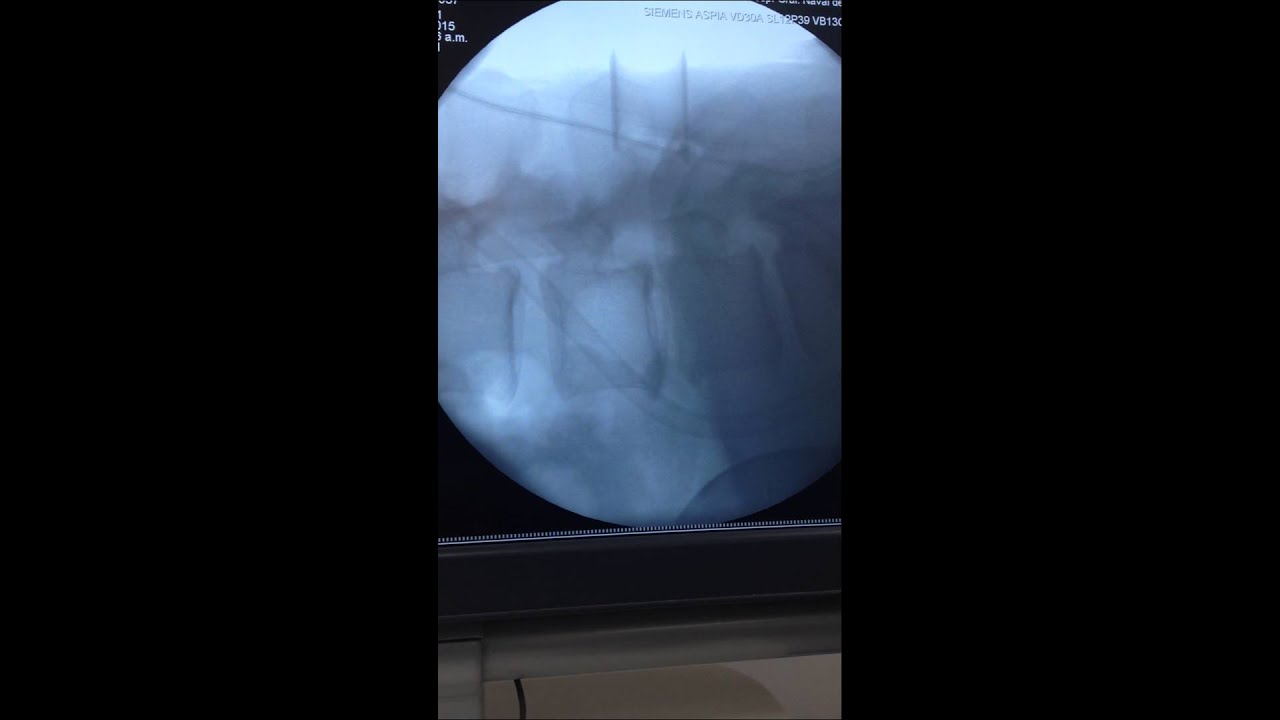

Reparación de fracturas o luxaciones del raquis

Reparación de fracturas y luxaciones de la columna cervical